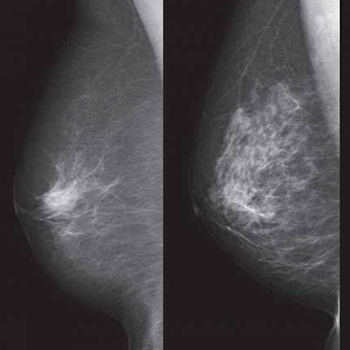

The model placed 31% of patients with future breast cancer in the top risk decile, versus the 18% seen with traditional models.